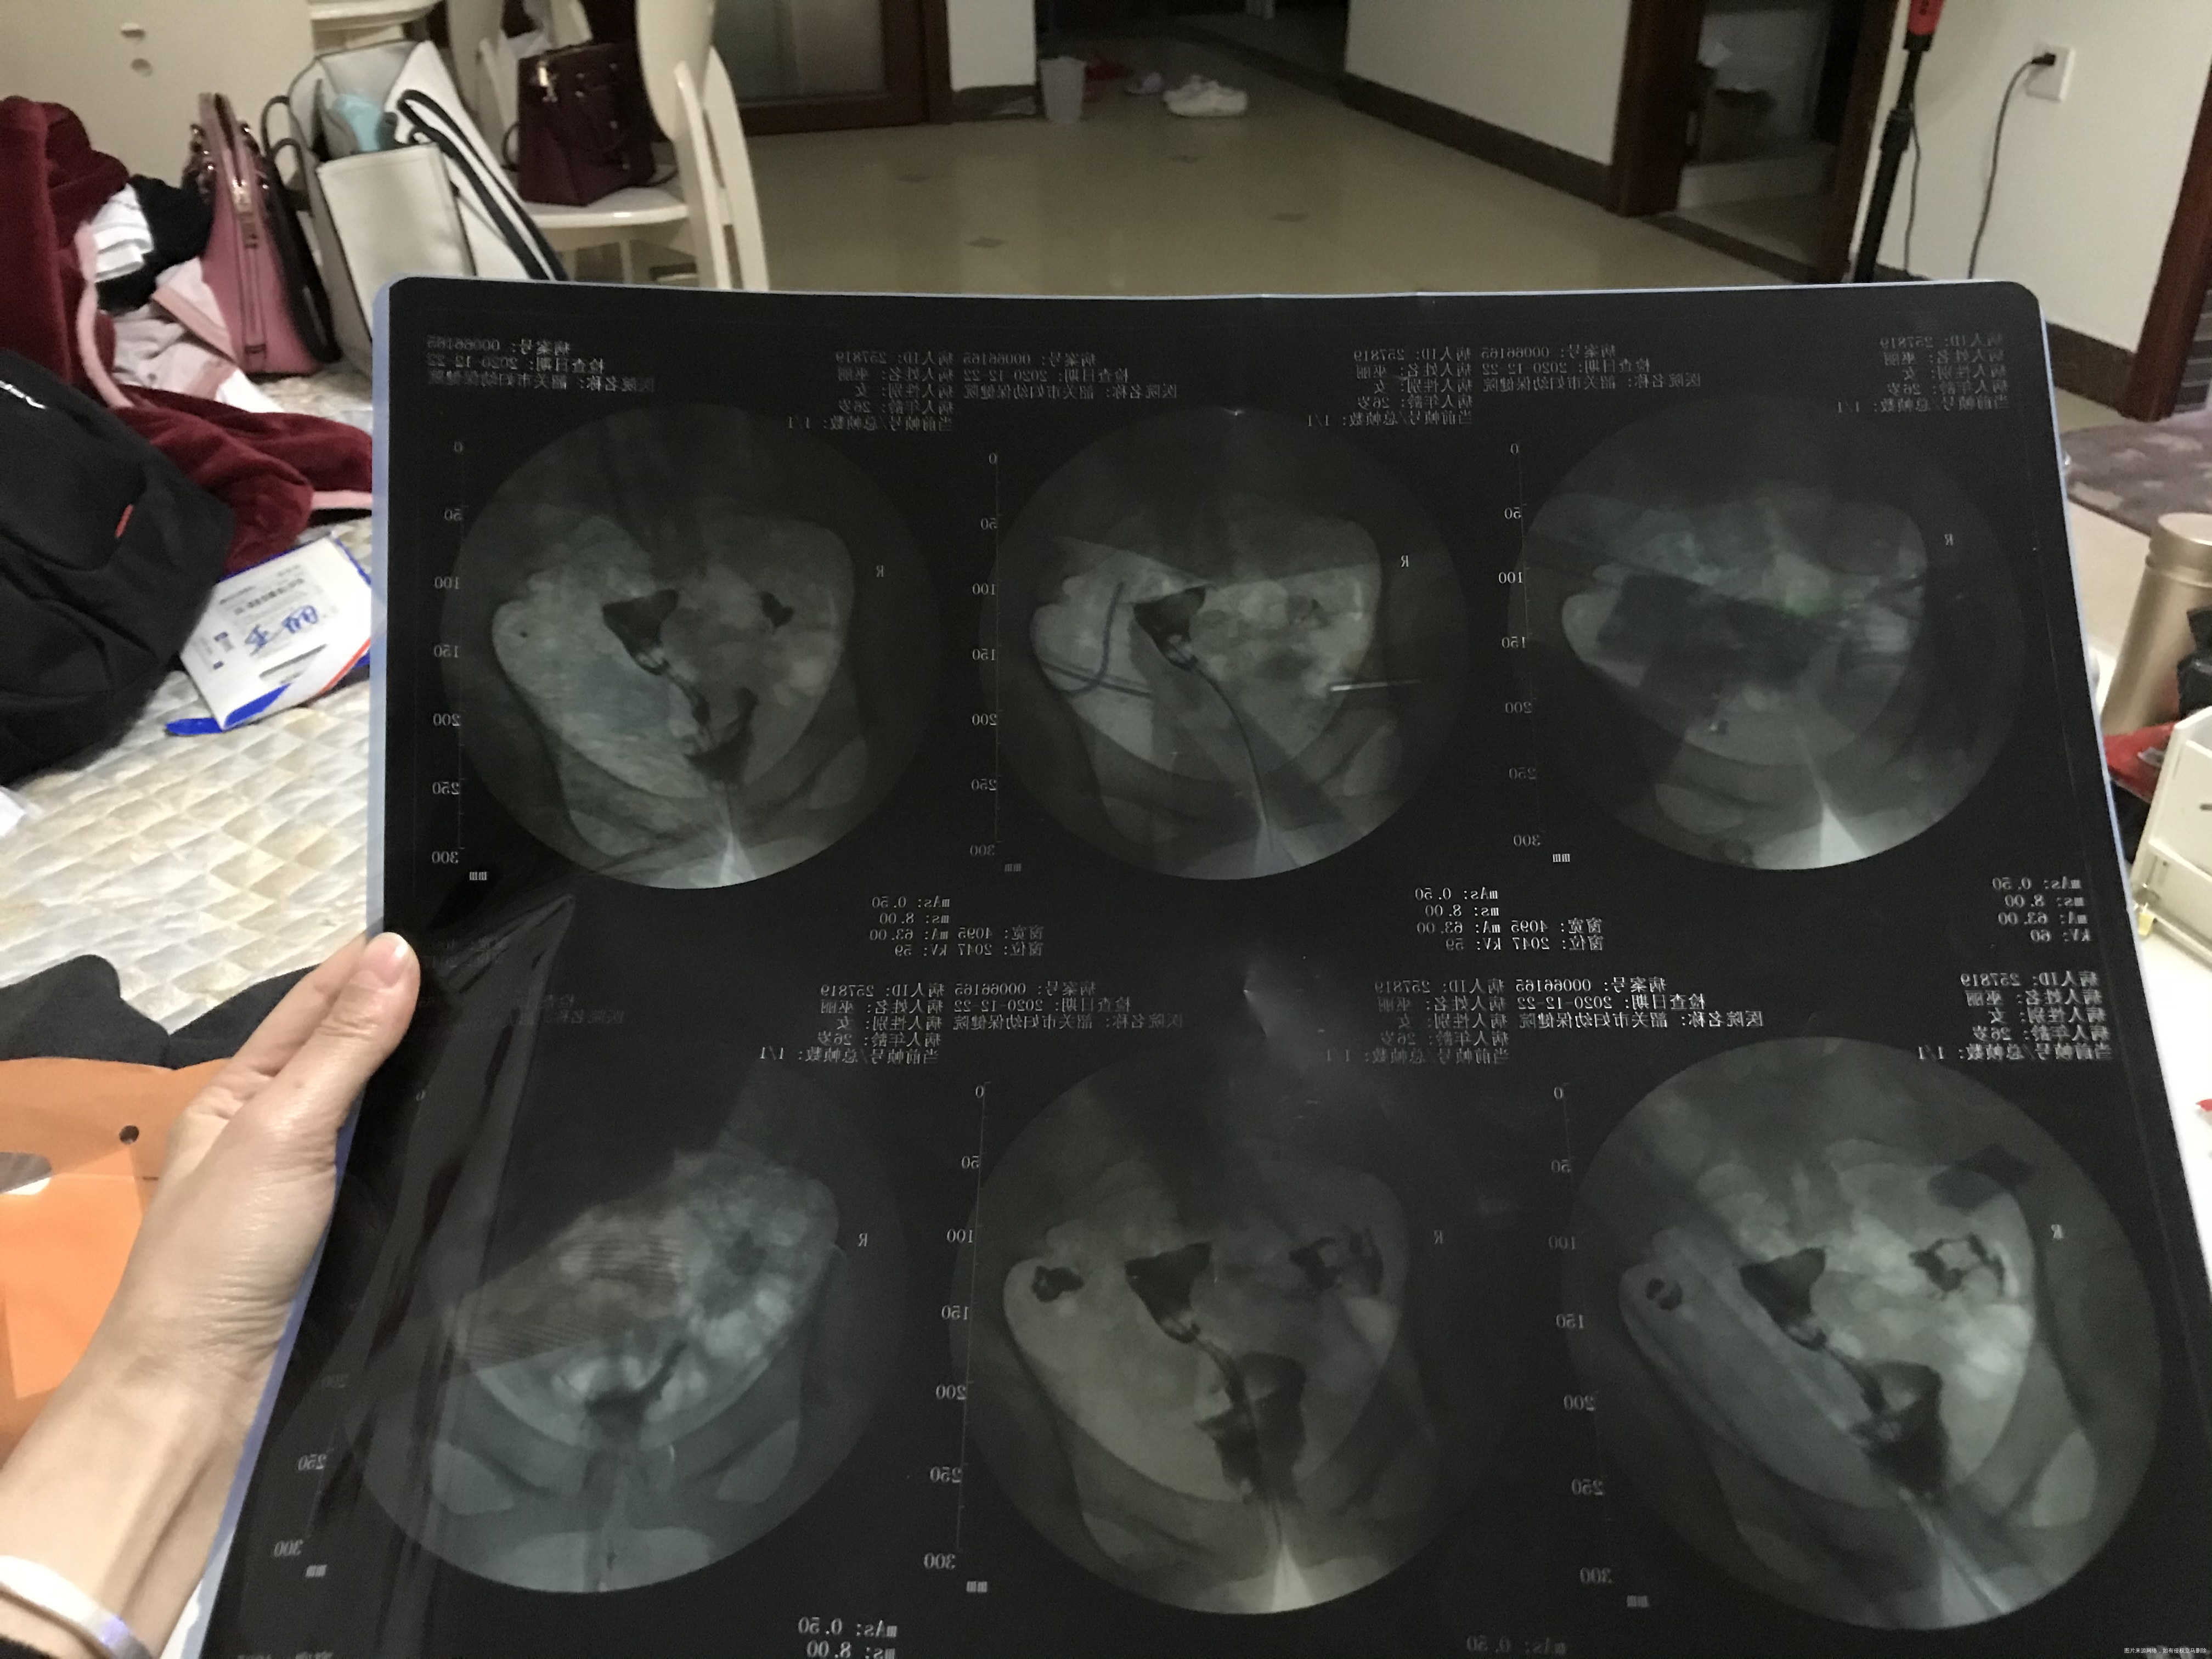

有医生看的懂造影单吗?拍的不是很清楚,麻烦帮我分析下谢谢

你好,看片子是一侧输卵管不通,一侧输卵管积水。建议试管助孕

做了输卵管造影吧,一侧不通,一侧有积水,可以尝试疏通术后备孕,但是怀孕几率不是很大,积水一侧基本上没有功能了,如果想快点,就直接试管婴儿技术助孕吧,一步到位,早点解决孩子问题。

苏占营 回复 匿名用户:移植前需要做结扎或者切除,以免影响胚胎着床。